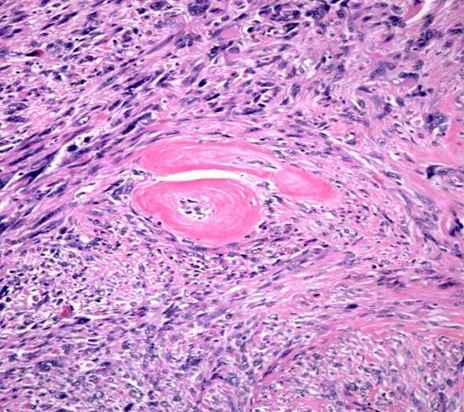

Microscopic (histologic) description

- Fumarate hydratase deficient leiomyoma:

- Alveolar edema

- Staghorn or hemangiopericytoma-like vessels

- Chain-like growth of tumor cells

- Spindle or epithelioid cells with ovoid nuclei and prominent eosinophilic nucleoli surrounded by perinucleolar halos

- Rhabdoid / eosinophilic cytoplasmic inclusions

- May include multinucleated cells and cells with bizarre nuclei

Microscopic (histologic) images

Contributed by Sabrina Croce, M.D., Ph.D., Kristina Doytcheva, M.D., Jennifer A. Bennett, M.D. (Case #508) and @Andrew_Fltv on Twitter